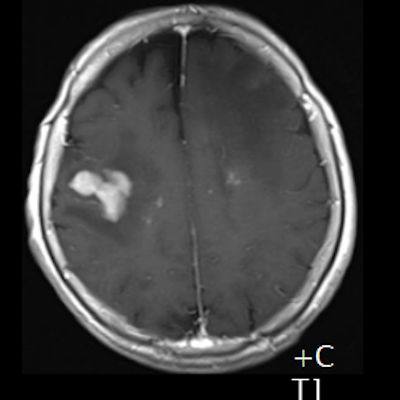

- (B) Aksiyel postkontrast T1A görüntülerde büyüğü sol frontalde kontrastlanma gösteren multipl kitle lezyonları (oklar) izlenmektedir.

- (C) Difüzyon ağırlıklı görüntülerde sol frontaldeki kitle lezyonunda difüzyon kısıtlama bulgusu (oklar) mevcut olup perfüzyon MRG’de rCBV haritasında belirgin perfüzyon artışı izlenmemektedir (ok).